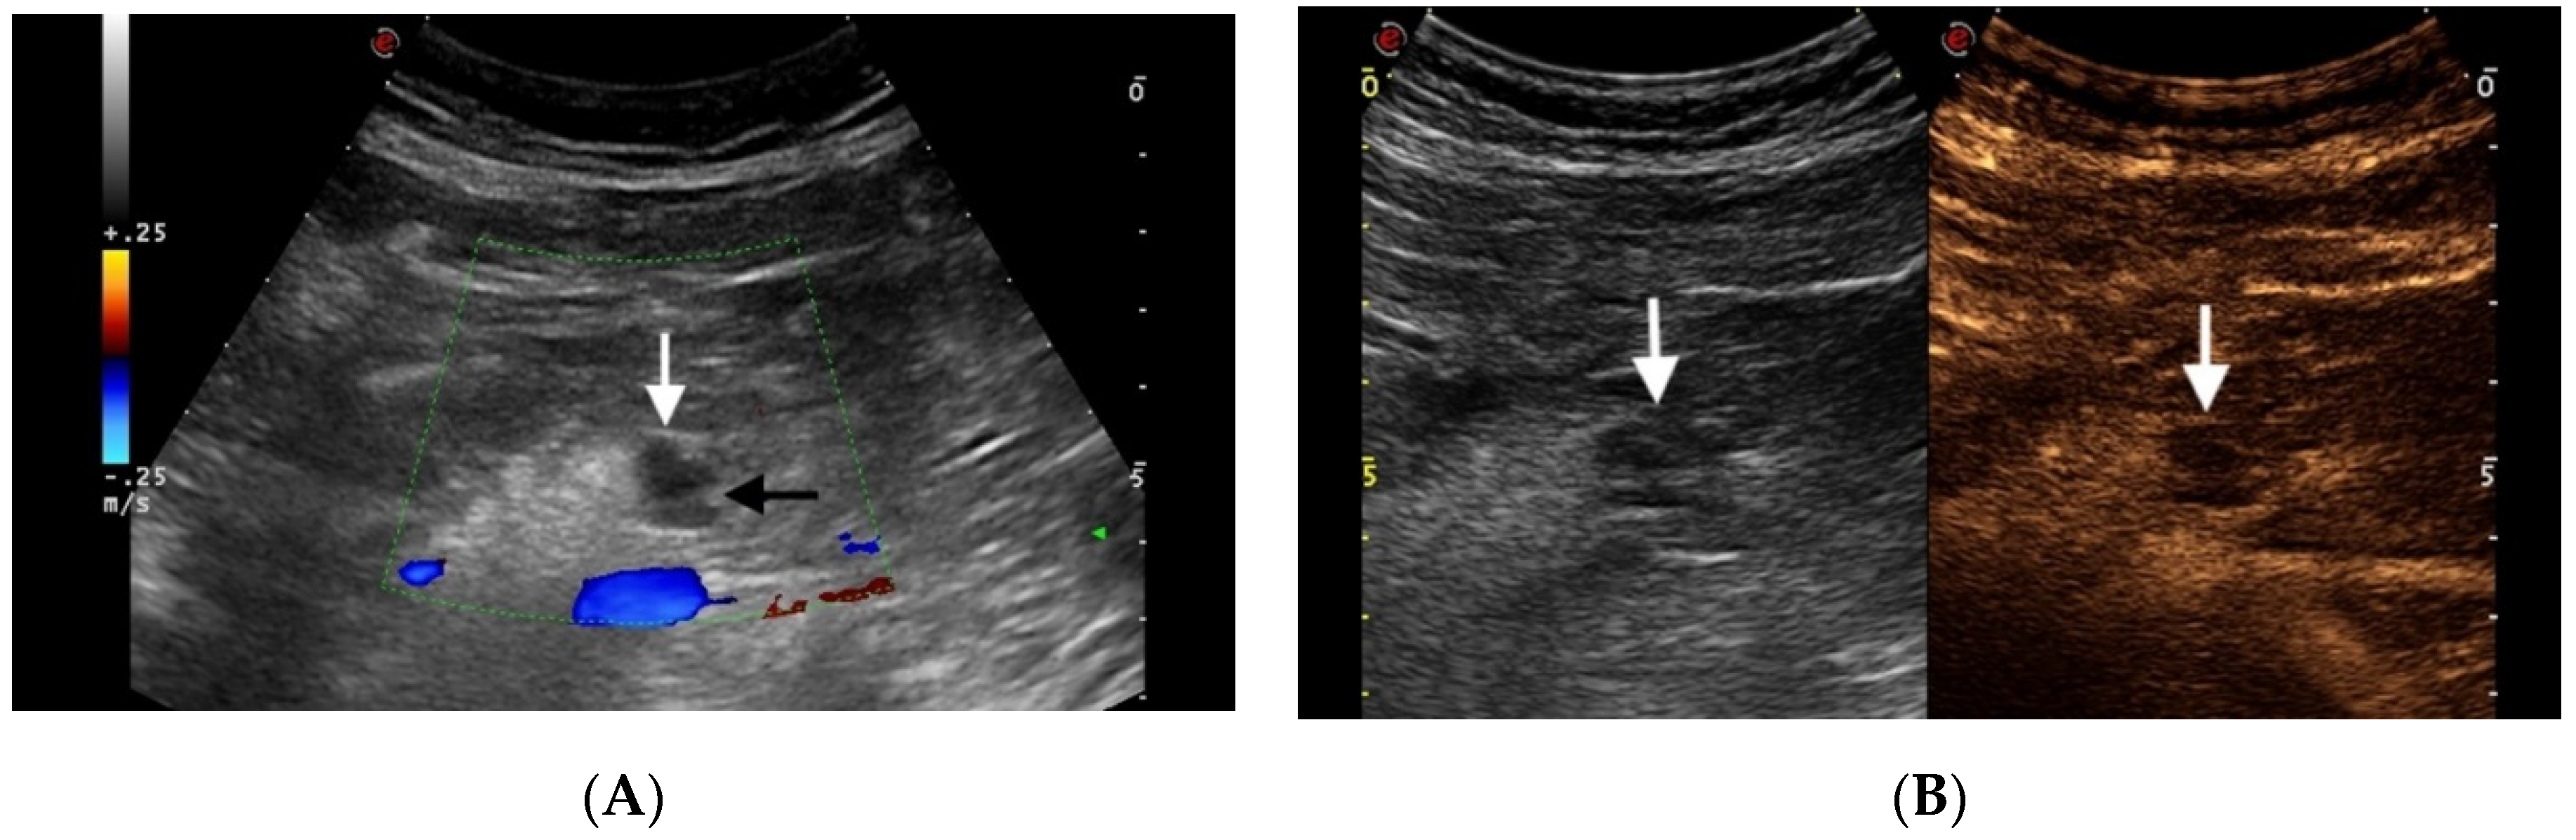

3.2. Pancreatic Neuroendocrine Tumors